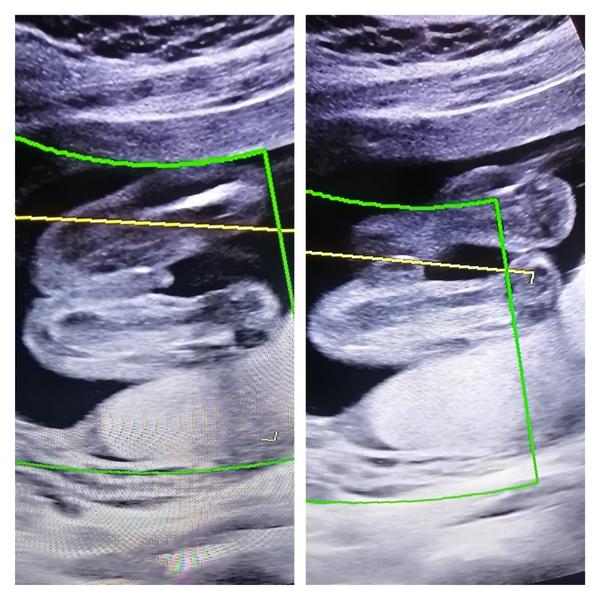

Zovna z tehle fotky to asi vidět není, ale jinak se pohlaví určuje právě z profilu a už od 6 cm to jde dobře u většiny určit.

Z tohohle to fakt nepůjde poznat. Mě vždycky doktor dal fotku, na které byl zadeček a pohlaví zespodu, jako kdyby pohled ze záchodové mísy.